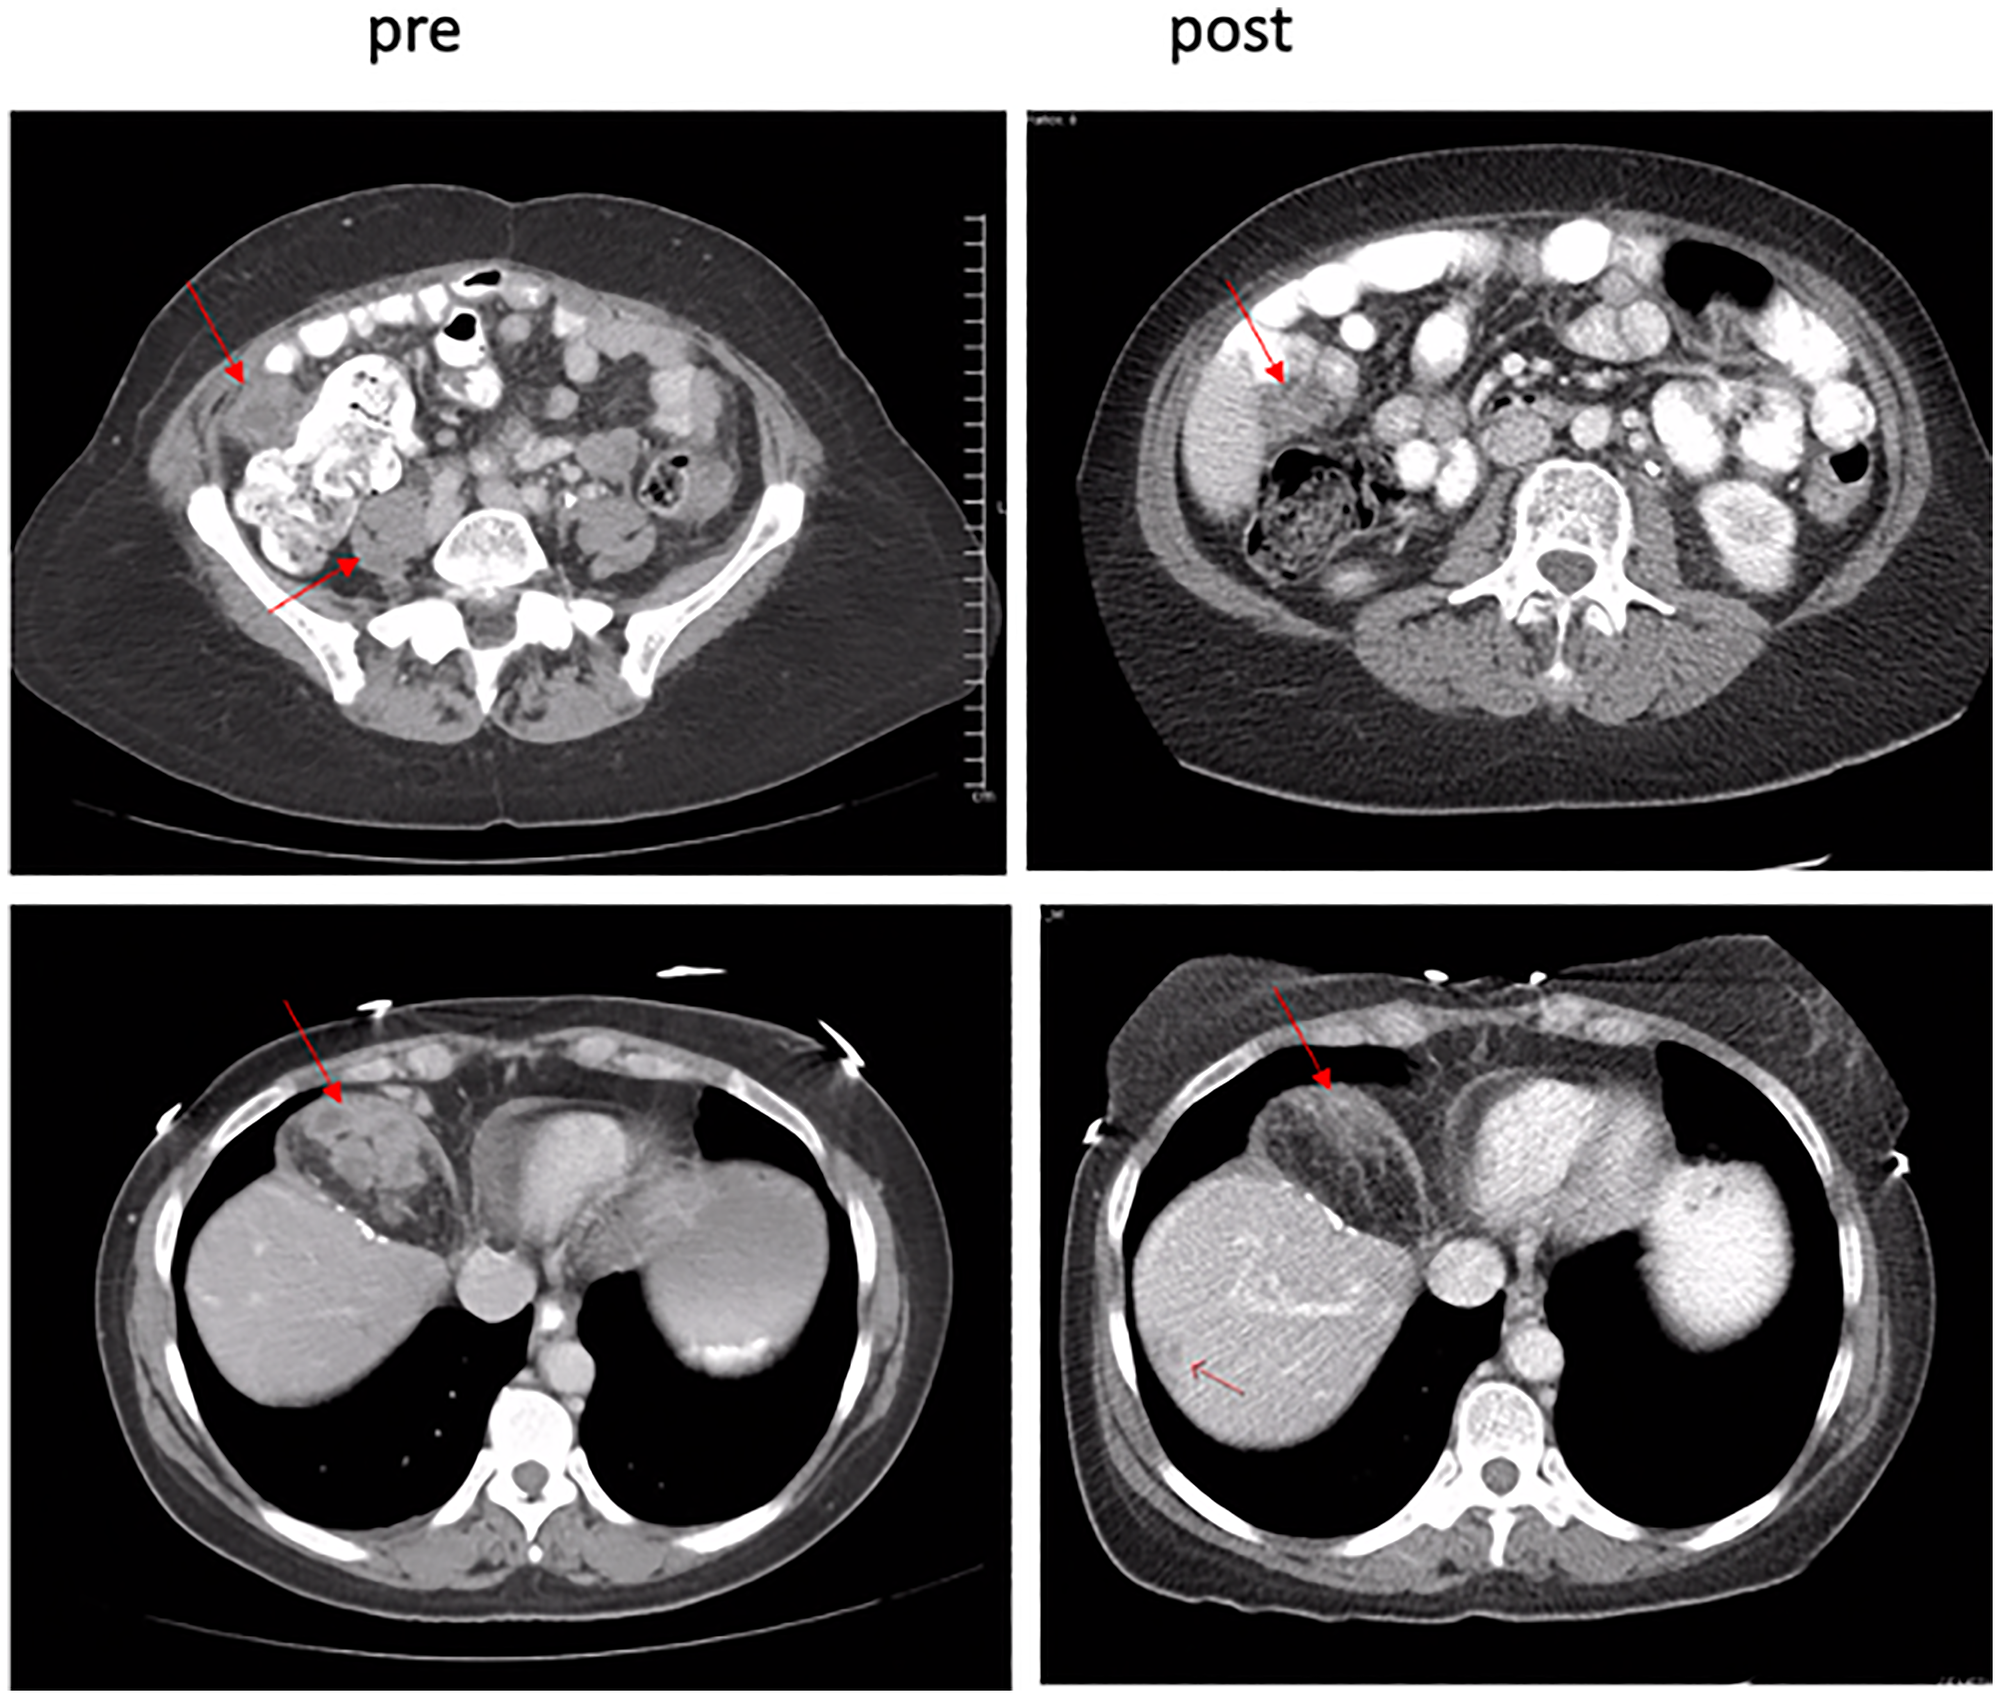

Thirty patients (86%) were evaluable for treatment efficacy and tumor response. Five patients discontinued protocol therapy prior to the first scan and were not evaluable. Two patients discontinued therapy due to adverse events possibly related to study treatment, one patient with grade 3 fatigue possibly related to riluzole or sorafenib, and one patient with grade 4 troponin elevation, grade 4 non-ST segment elevation myocardial infarction (NSTEMI), and grade 3 congestive heart failure in the setting of a prior history of coronary artery disease (CAD). The remaining three patients discontinued therapy for non-treatment related reasons, including 1 patient who discontinued treatment due to a hip fracture that was unrelated to treatment, and 2 patients who were discontinued due to protocol nonadherence. Eleven patients (36%) experienced stable disease. The median time from on study to date of progression was 106 days (range 51–240 days) or 3.5 months (range 1.7–8.0 months). Only one patient had stable disease for over six months, a patient with a metastatic gastrointestinal stromal tumor (GIST) previously treated with imatinib, nilotinib, and sunitinib who was on protocol therapy for 8 months before progression. Eighteen patients (51%) experienced progressive disease. One patient with metastatic pancreatic acinar cell cancer experienced a partial response lasting 264 days (8.8 months) (Figure 1). The median number of months on trial was 3.3 (range 1.4–9.2 months).

Pre- and post-treatment scans confirmed partial responder

Figure 1: Pre- and post-treatment scans confirmed partial responder. A 39.9% decrease in target lesions was observed after C2D1.

Although the majority of patients had progressive disease with this combination (51%), one patient with pancreatic acinar cell carcinoma with metastases to the liver and mesenteric lymph nodes whose tumor harbored a KANK4-RAF1 fusion identified by next generation sequencing achieved a partial response that encouragingly lasted for over 8 months. This patient was heavily pretreated with multiple (>5) prior lines of chemotherapy as well as chemoembolization of liver metastases, none of which resulted in a clinical response. In addition to a radiologic and clinical response, this patient displayed statistically significant decreases in GRM1, AKT, and pro-apoptotic protein BIM in analyses of paired tumor tissue, supporting target engagement and activity. The clinical response sustained over several months and the almost 4-fold increase in BIM levels post-treatment in this patient suggests further investigation of this combination in a pre-specified subset of patients may be warranted.